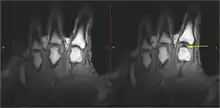

- Cavitation within the joint—small cavities of partial vacuum form in the synovial fluid and then rapidly collapse, producing a sharp sound.[6][7]

There were several hypotheses to explain the cracking of joints. Synovial fluid cavitation has some evidence to support it.[10] When a spinal manipulation is performed, the applied force separates the articular surfaces of a fully encapsulated synovial joint, which in turn creates a reduction in pressure within the joint cavity. In this low-pressure environment, some of the gases that are dissolved in the synovial fluid (which are naturally found in all bodily fluids) leave the solution, making a bubble, or cavity (tribonucleation), which rapidly collapses upon itself, resulting in a "clicking" sound.[11] The contents of the resultant gas bubble are thought to be mainly carbon dioxide, oxygen and nitrogen.[12] The effects of this process will remain for a period of time known as the "refractory period", during which the joint cannot be "re-cracked", which lasts about 20 minutes, while the gases are slowly reabsorbed into the synovial fluid. There is some evidence that ligament laxity may be associated with an increased tendency to cavitate.[13]

In 2015, research showed that bubbles remained in the fluid after cracking, suggesting that the cracking sound was produced when the bubble within the joint was formed, not when it collapsed.[9] In 2018, a team in France created a mathematical simulation of what happens in a joint just before it cracks. The team concluded that the sound is caused by bubbles' collapse, and bubbles observed in the fluid are the result of a partial collapse. Due to the theoretical basis and lack of physical experimentation, the scientific community is still not fully convinced of this conclusion.[3][14][15]